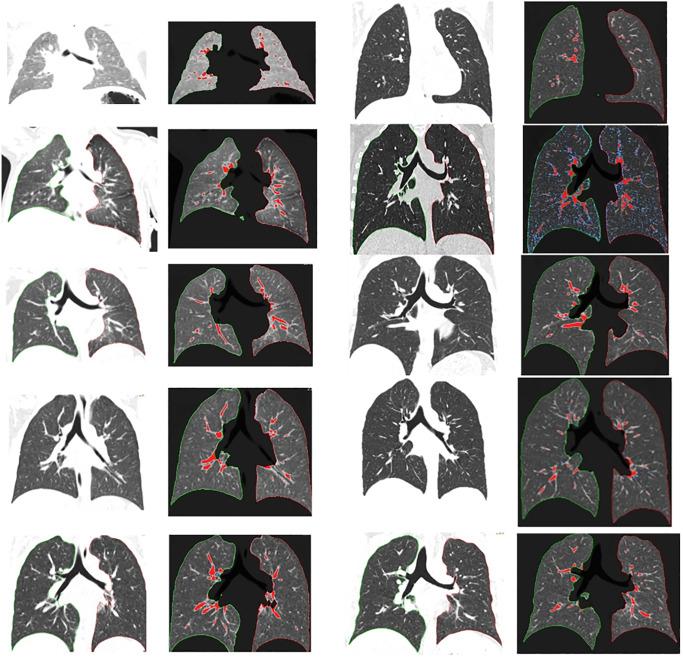

Quantified computed tomography (qCT) is known for correlations with airflow obstruction and fibrotic changes of the lung. However, as qCT studies often focus on diseased and elderly subjects, current literature lacks physiological qCT values during body development. We evaluated chest CT examinations of a healthy cohort, reaching from infancy to adulthood, to determine physiological qCT values and changes during body development.

METHOD

Dose-optimized chest CT examinations performed over the last 3 years using a dual-source CT were retrospectively analysed. Exclusion criteria were age >30 years and any known or newly diagnosed lung pathology. Lung volume, mean lung density, full-width-at-half-maximum and low attenuated volume (LAV) were semi-automated quantified in 151 patients. qCT values between different age groups as well as unenhanced (Group 1) and contrast-enhanced (Group 2) protocols were compared. Models for projection of age-dependant changes in qCT values were fitted.

定量计算机断层扫描(qCT)与气流阻塞和肺部纤维化改变相关。然而,由于 qCT 研究通常集中在患病和老年患者身上,目前的文献缺乏身体发育过程中的生理 qCT 值。我们评估了健康队列的胸部 CT 检查,从婴儿期到成年期,以确定生理 qCT 值和身体发育过程中的变化。

方法

回顾性分析了过去 3 年使用双源 CT 进行的剂量优化胸部 CT 检查。排除标准为年龄>30 岁和任何已知或新诊断的肺部病理学。在 151 名患者中,使用半自动方法对肺容积、平均肺密度、半高全宽和低衰减体积(LAV)进行定量。比较了不同年龄组之间以及未增强(第 1 组)和增强(第 2 组)方案之间的 qCT 值。拟合了用于预测 qCT 值与年龄相关变化的模型。